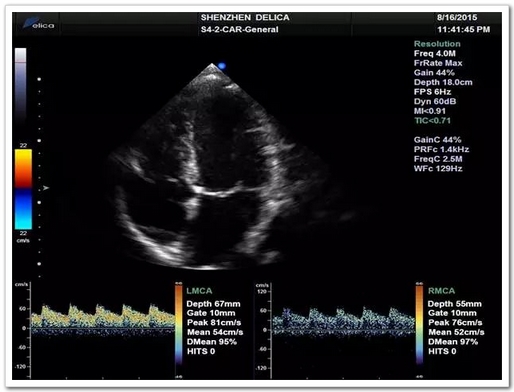

張阿姨血管評(píng)估并未發(fā)現(xiàn)頭頸部血管狹窄的證據(jù),考慮原因不明性卒中,進(jìn)一步行TCD發(fā)泡試驗(yàn):提示發(fā)泡試驗(yàn)陽(yáng)性-支持右向左分流(固有型,大量)。建議完善經(jīng)食道心臟超聲。

圖3:TCD發(fā)泡實(shí)驗(yàn)(德力凱)

經(jīng)食道心臟超聲:提示卵圓孔未閉(PFO),裂縫寬約3mm。

至此,張阿姨腦梗死的病因罪魁禍?zhǔn)卓紤]來(lái)自于心臟卵圓孔未閉。TCD發(fā)泡試驗(yàn)可以幫助尋找這類(lèi)病因。